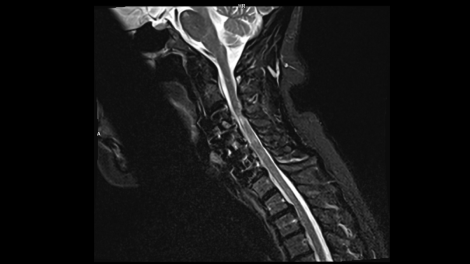

Whether it is head, neck, spine, abdomen or MSK – our clinical experts have complete confidence in the ability of MAGNETOM Free.Max to deliver excellent diagnostic quality for all these standard clinical MRI applications.